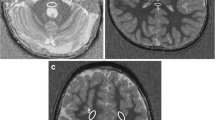

To study the MT phenomenon, a three-dimensional (3D) gradient echo sequence (TR/TE 32/8, flip angle 6°) was performed, and 4-mm/2-mm overlapping sections were concurrently obtained both with and without the application of MT binomial prepulse applied on-resonance. Images of this sequence obtained before application of MT prepulse had proton-density contrast due to the short TE and small flip angle (Fig. 1a). The MT sequence performed in the axial plane (perpendicular to the intercommisural line, i.e., the anterior commissure to posterior commissure line, or AC-PC line) was part of our standard protocol. Images obtained after application of the MT prepulse depict structures of high MTR with low signal intensity and those of low MTR with higher intensity (Fig. 1b). The duration of a complete MR examination ranged from 15 to 25 min. MTRs were calculated from circular regions of interest (ROIs), with a minimum size of 0.5 mm2. In all cases, UBOs observed on T2-weighted images were also detectable in proton density images of the MT sequence; therefore, ROIs were positioned at an image without MT and copy–pasted to the corresponding image with MT. Signal intensity measurements were performed bilaterally in the following regions: cortex and WM of the frontal and occipital lobe, caudate nucleus, putamen, globus pallidus, thalamus, optic chiasm, internal capsule, genu and splenium of the CC, hippocampus, cerebral peduncles, and cerebellar WM. Care was taken to avoid the partial volume effect of CSF when defining ROIs. MTR was calculated as: (SI0-SIm)/SI0×100% where SI0 is the signal intensity from the image acquired without a MT pre-pulse and SIm refers to signal intensity from an image acquired with MT prepulse.